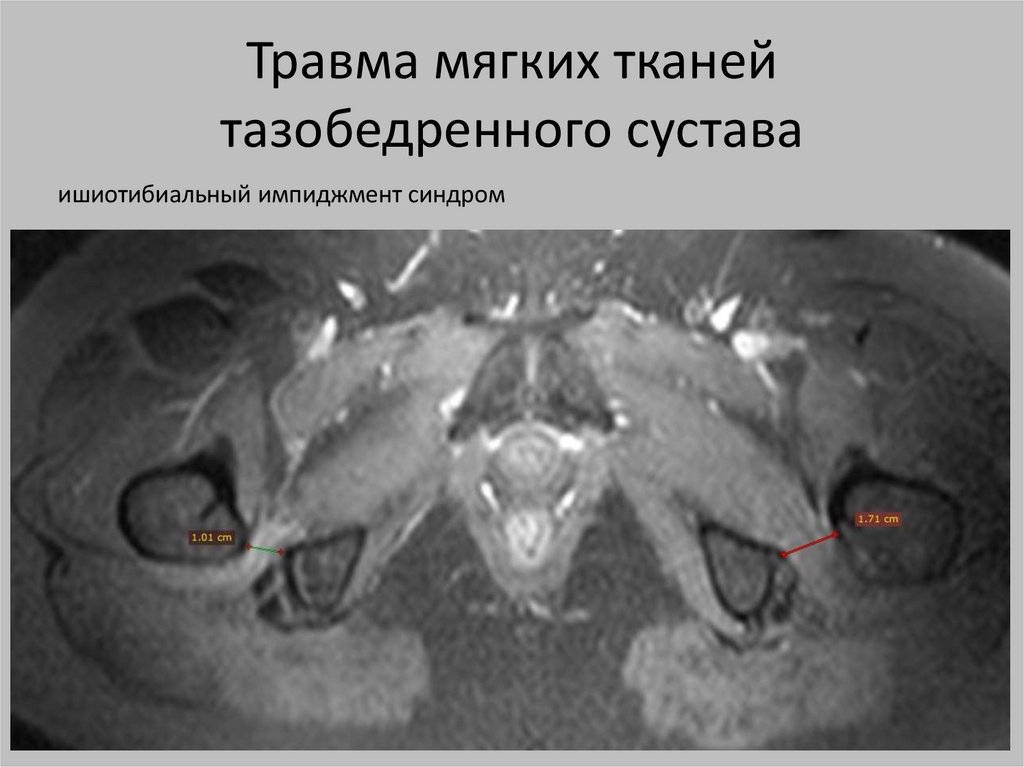

Травма мягких тканей

тазобедренного сустава

ишиотибиальный импиджмент синдром